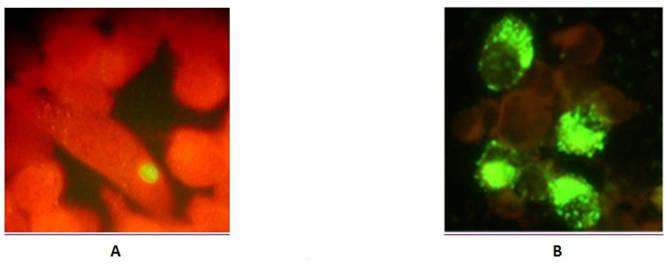

16000 g pellet fraction of serum specimens obtained from 38 patients with ACS were resuspended and inoculated into cycloheximide-treated HL cells for further culture assay and immunofluroscence analysis with chlamydial LPS-specific antibody. A total of 8 specimens from ACS patients were positive for chlamydial growth with LPS-specific antibody revealing the presence of viable C. pneumoniae in serum. Positive immunofluorescence was usually seen within 72 hours after specimen inoculation. Inclusions varied in size and staining but were generally much smaller, than usually seen in case of C. pneumoniae infection in cultured cells and had reduced intensity of immunofluorescent staining (Figure 5) resembling those reported during persistent C pneumoniae infection in presence of IFN-γ (26).

Figure 5

Immunofluoresence analysis of HL monolayers after inoculation of serum sediments (A), and reference culture (B) of C. pneumoniae.